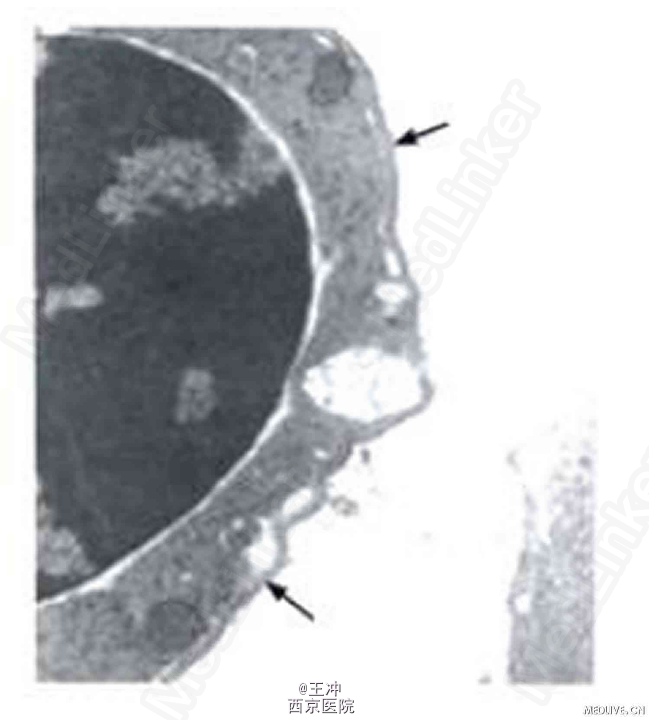

患者女,32岁,汉,因“巩膜黄染、面色苍黄20余年”入院。自幼巩膜黄染、面色苍黄,外周血HGB波动于60~80g/L,多方就诊未明确诊断。1个月前因“胆囊炎”查WBC 4.7×109/L,HGB 71 g/L,PLT 273×109/L。骨髓红系细胞比例占0.712。B超示脾脏肿大。疑溶血性疾病转至我院。 既往史无特殊。月经正常,7年前生育一正常男婴。父母及两位胞姐无类似症状。 查体:发育正常,贫血貌,巩膜黄染。心、肺未见异常。肝肋缘下2 cm,脾肋缘下未触及。 血常规:WBC 4.94×109/L,HGB 70 g/L,PLT 280×109/L.红细胞平均体积(MCV)98.1 fl,红细胞平均血红蛋白浓度(MCHC)330 g/L,网织红细胞(Ret)1.59%,Ret绝对值0.0343 x1012/L。 骨髓组织病理检查:增生极度活跃,粒红比例减小。 结合病史及实验室检查,确诊为CDA-Ⅱ即先天性红细胞生成异常性贫血II型。